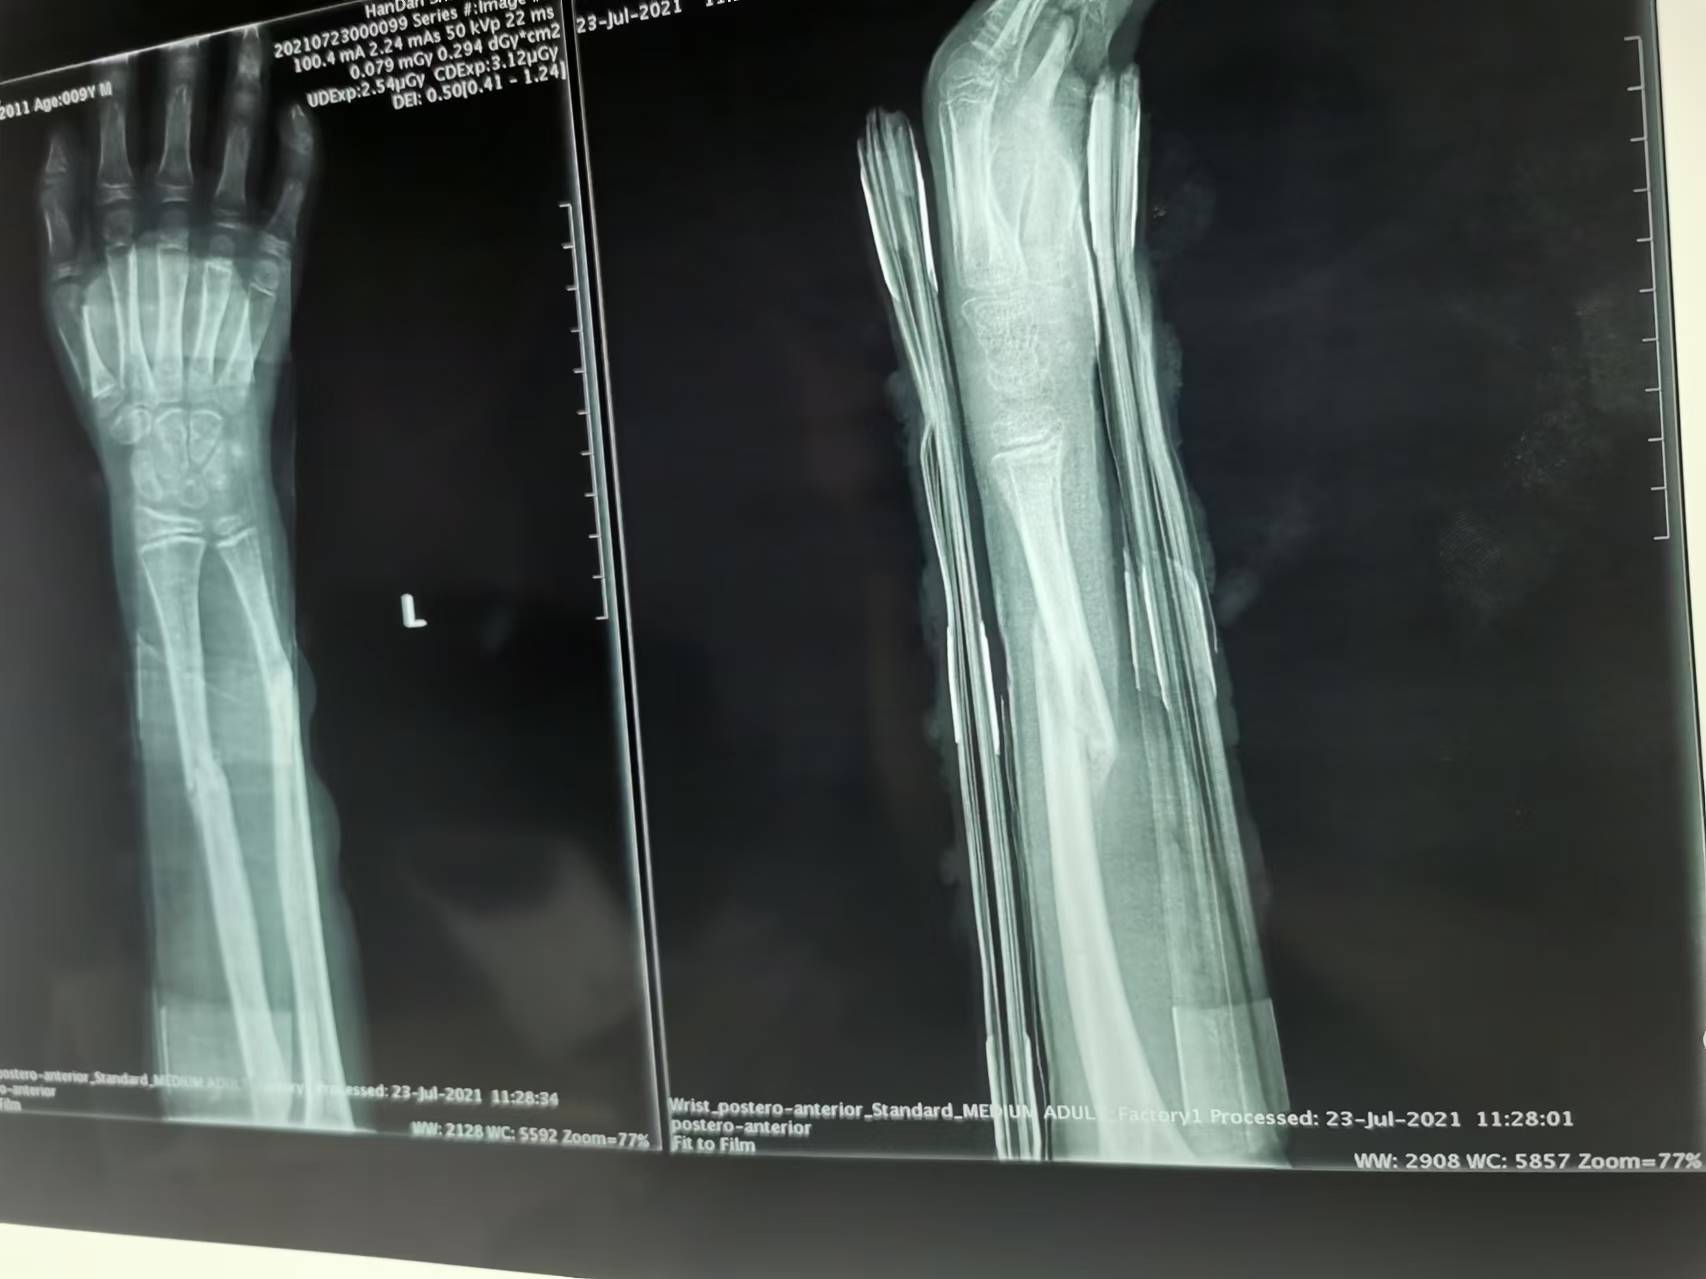

首页 > 张恒云工作室 > 影像资料 三